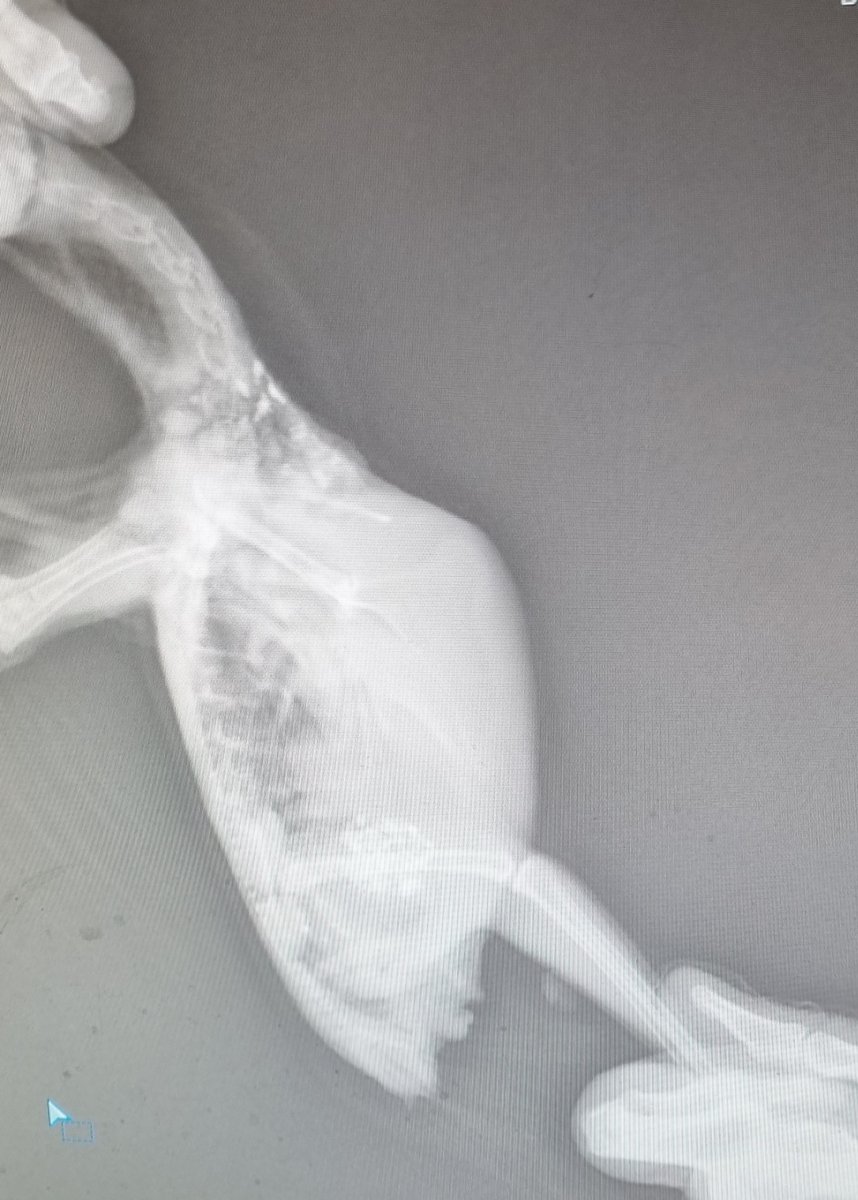

Зравствуйте. Переделали ренген. Помет при отмене всех лекарств лучше. Но картина на ренгене нет

20221009_124542.jpg

20221009_124621.jpg

но сейчас я сделала латеральную проекцию.

да, почки сильно не в порядке.

и голова, и хвост- очень яркие.

714019041_.thumb.png.ee30528b9ae2623773cfe7b526d9c343.png